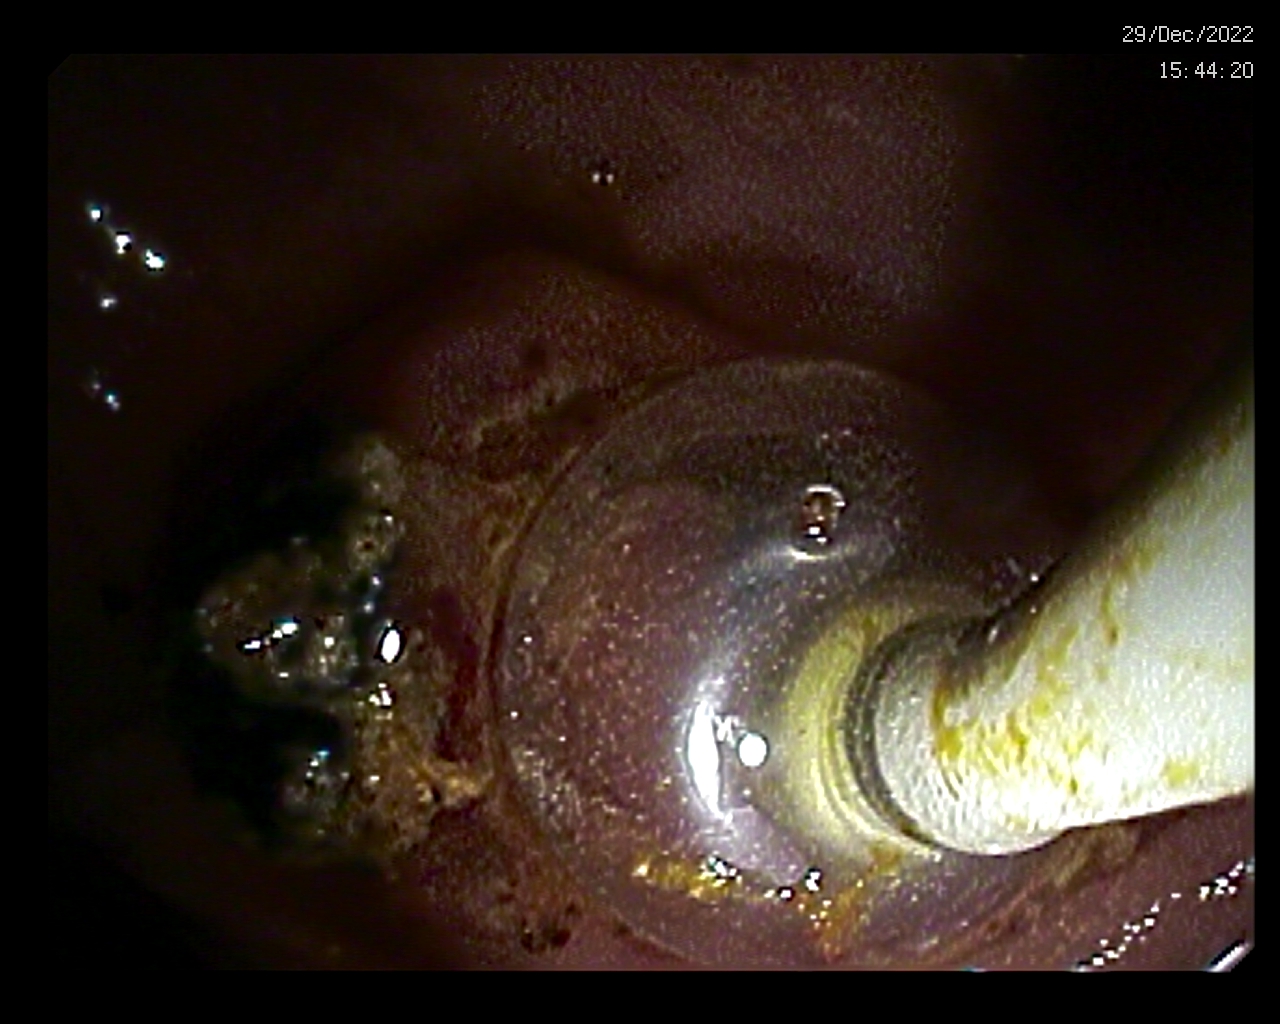

Dicha técnica se realiza con un tipo de duodenoscopio que tiene una visión lateral, lo cual permite explorar de forma frontal el área anatómica por la que drena la bilis al duodeno a través de los conductos biliares (y que en una gastroscopia apenas se ve correctamente o en su totalidad al quedar en una visión lateralizada). A través del canal de trabajo del duodenoscopio, se pueden pasar diferentes instrumentos (esfinterotomos, balones de dilatación, balones de extracción o Fogarty o prótesis plásticas o metálicas) lo que permite la realización de diferentes terapéuticas.

La CPRE, por tanto, es una técnica terapéutica, no diagnóstica (para ello, estarían la Colangio- Resonancia Magnética o Colangio-RNM o la Ecoendoscopia). Mediante dicha exploración se valora minuciosamente los tramos mencionados, permitiendo el tratamiento de distintas patologías que cursan con ictericia obstructiva (tinte amarillento de la piel por obstrucción a nivel de los conductos biliares) como litiasis en los conductos, generalmente en el colédoco (coledocolitiasis), estrecheces o estenosis (benignas o malignas) de los mismos, ya sean internas o por compresión de lesiones (fundamentalmente tumores de la cabeza pancreática), o lesiones tumorales en los mismos (colangiocarcinomas), entre otros.